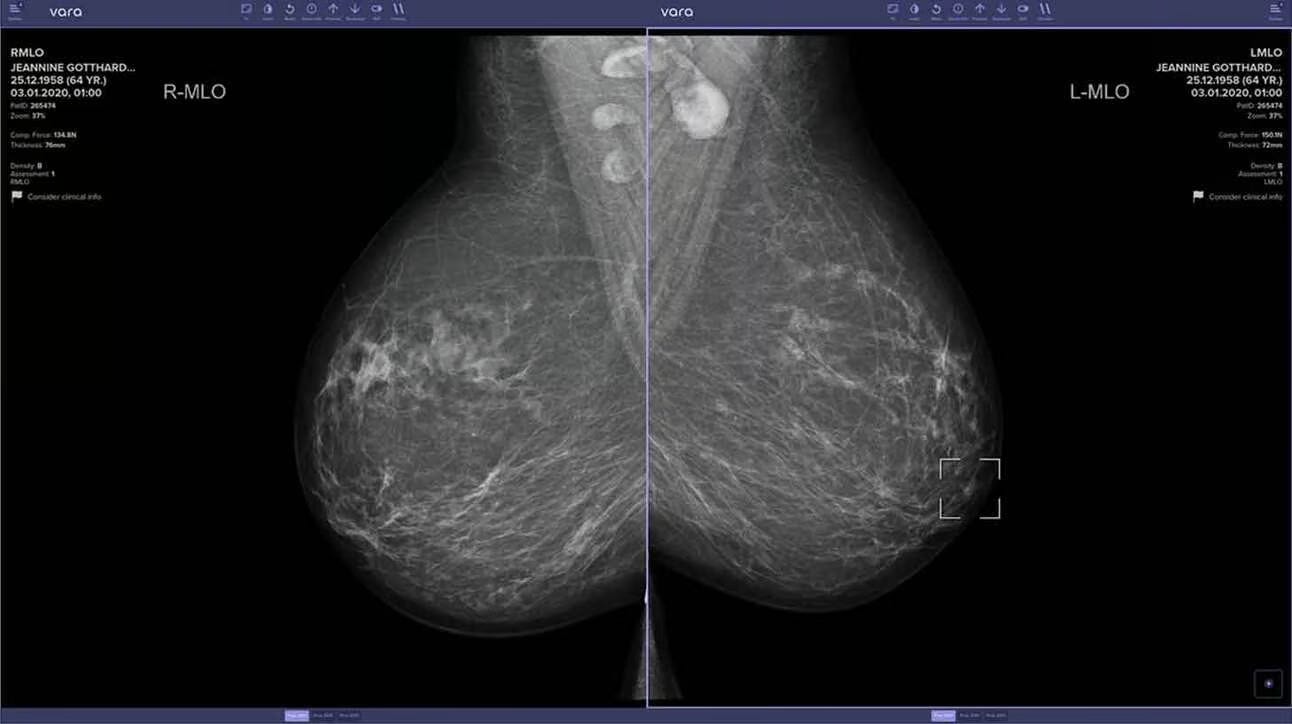

🔬 AI TĂNG CƯỜNG PHÁT HIỆN UNG THƯ TRONG NGHIÊN CỨU MANG TÍNH BƯỚC NGOẶT

Nguồn hình ảnh: Đại học Lubeck

Một bước đột phá mới trong y học! Các nhà nghiên cứu từ Đại học Lubeck (Đức) vừa thực hiện ứng dụng AI quy mô lớn nhất từ trước đến nay trong sàng lọc ung thư vú – và kết quả thật đáng kinh ngạc: AI có thể nâng cao tỷ lệ phát hiện ung thư vú lên hơn 17%, mở ra hy vọng mới cho hàng triệu bệnh nhân.

Nghiên cứu liên quan đến 119 bác sĩ X quang có thể tự nguyện chọn hoặc không sử dụng AI, với hơn 460.000 phụ nữ trải qua sàng lọc.

Bác sĩ X quang hỗ trợ AI đạt được tỷ lệ phát hiện ung thư là 6.7 trên 1.000 sàng lọc, cải thiện 17.6% so với cách đọc truyền thống.

Đối với các sinh thiết được đặt hàng, 65% các lần đọc có hỗ trợ AI xác nhận ung thư so với 59% mà không có, cho thấy độ chính xác cải thiện trong việc đề xuất các thủ tục.

AI cũng giúp giảm tải công việc bằng cách cho phép thời gian đọc nhanh hơn 43% trong khi duy trì độ chính xác, từ 30 giây mỗi trường hợp xuống chỉ còn 16 giây.

Tại sao điều này quan trọng: AI đang thay đổi hoàn toàn ngành y! Từ việc thiết kế phương pháp điều trị tiên tiến đến hỗ trợ bác sĩ chẩn đoán chính xác hơn, công nghệ này đang nhanh chóng trở thành một công cụ không thể thiếu. Nhưng điều gì sẽ xảy ra nếu một bác sĩ từ chối sử dụng AI? Trong tương lai gần, đó có thể là một bất lợi lớn – và sức khỏe của bệnh nhân có thể bị ảnh hưởng.